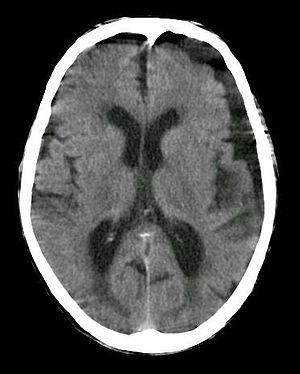

Subdural hygroma, frontal and temporal. Man of 80 years old.

A subdural hygroma (SDG) is a collection of cerebrospinal fluid (CSF), without blood, located under the dural membrane of the brain. Most subdural hygromas are believed to be derived from chronic subdural hematomas. They are commonly seen in elderly people after minor trauma but can also be seen in children following infection or trauma. One of the common causes of subdural hygroma is a sudden decrease in pressure as a result of placing a ventricular shunt. This can lead to leakage of CSF into the subdural space especially in cases with moderate to severe brain atrophy. In these cases the symptoms such as mild fever, headache, drowsiness and confusion can be seen, which are relieved by draining this subdural fluid.

In the majority of cases, if there has not been any acute trauma or severe neurologic symptoms, a small subdural hygroma on the head CT scan will be an incidental finding. If there is an associated localized mass effect that may explain the clinical symptoms, or concern for a potential chronic SDH that could rebleed, then an MRI, with or without neurologic consultation, may be useful.

It is not uncommon for chronic subdural hematomas (SDHs) on CT reports for scans of the head to be misinterpreted as subdural hygromas, and vice versa. Magnetic resonance imaging (MRI) should be done to differentiate a chronic SDH from a subdural hygroma, when clinically warranted. Elderly patients with marked cerebral atrophy, and secondary widened subarachnoid CSF spaces, can also cause confusion on CT. To distinguish chronic subdural hygromas from simple brain atrophy and CSF space expansion, a gadolinium-enhanced MRI can be performed. Visualization of cortical veins traversing the collection favors a widened subarachnoid space as seen in brain atrophy, whereas subdural hygromas will displace the cortex and cortical veins.